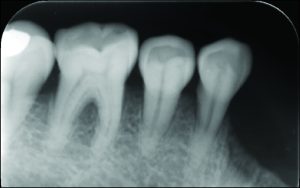

Periodontal preparation is usually performed in the period following oral surgical procedures. However, when the patient’s calculus accumulation is excessive, it is advisable to perform a gross debridement before tooth extraction to avoid causing infection. Periodontal treatment must be completed before restorative treatment. The remaining teeth, especially those with RPD abutments, should be evaluated for periodontal support and treated.

The use of direct retainers on isolated abutment teeth in distal extension PRD cases usually accelerates the destruction of the periodontium, leading to tooth loss. For this reason, it is recommended to place rests on isolated teeth and not to use direct retainers. Another option is restoration of the modification space with a fixed partial denture and splinting of the teeth (Figures 10-15).